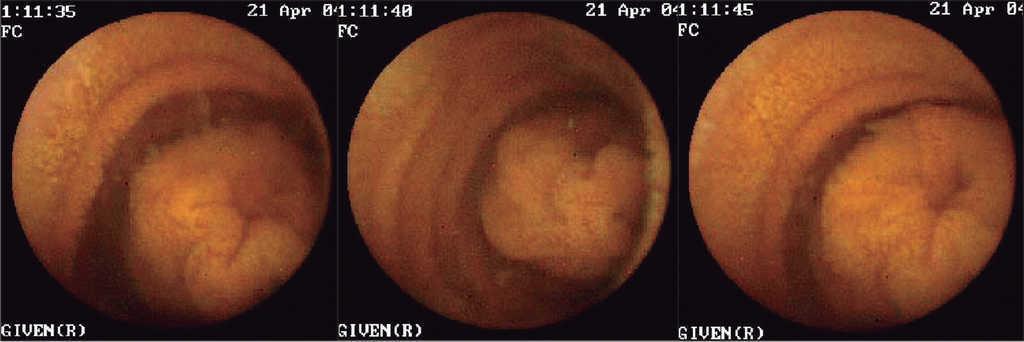

En el 43,75 % de los pacientes estudiados (7/16) la CE mostró lesiones sugerentes de hiperplasia nodular linfoide principalmente en íleon (fig. 1). En un paciente se observó una invaginación intestinal que creemos que no tiene significación clínica alguna (fig. 2). En otro niño se observó un sangrado leve en ciego que no fue corroborado por una nueva ileocolonoscopia. En una niña se observaron oxiuros en ciego (fig. 3) y en otra, la CE mostró lesiones aftoides en íleon sugerentes de enfermedad de Crohn (fig. 4).

Figura 2. Imagen de invaginación intestinal. Se observa cómo la mucosa del íleon distal se introduce dentro de la del íleon proximal.